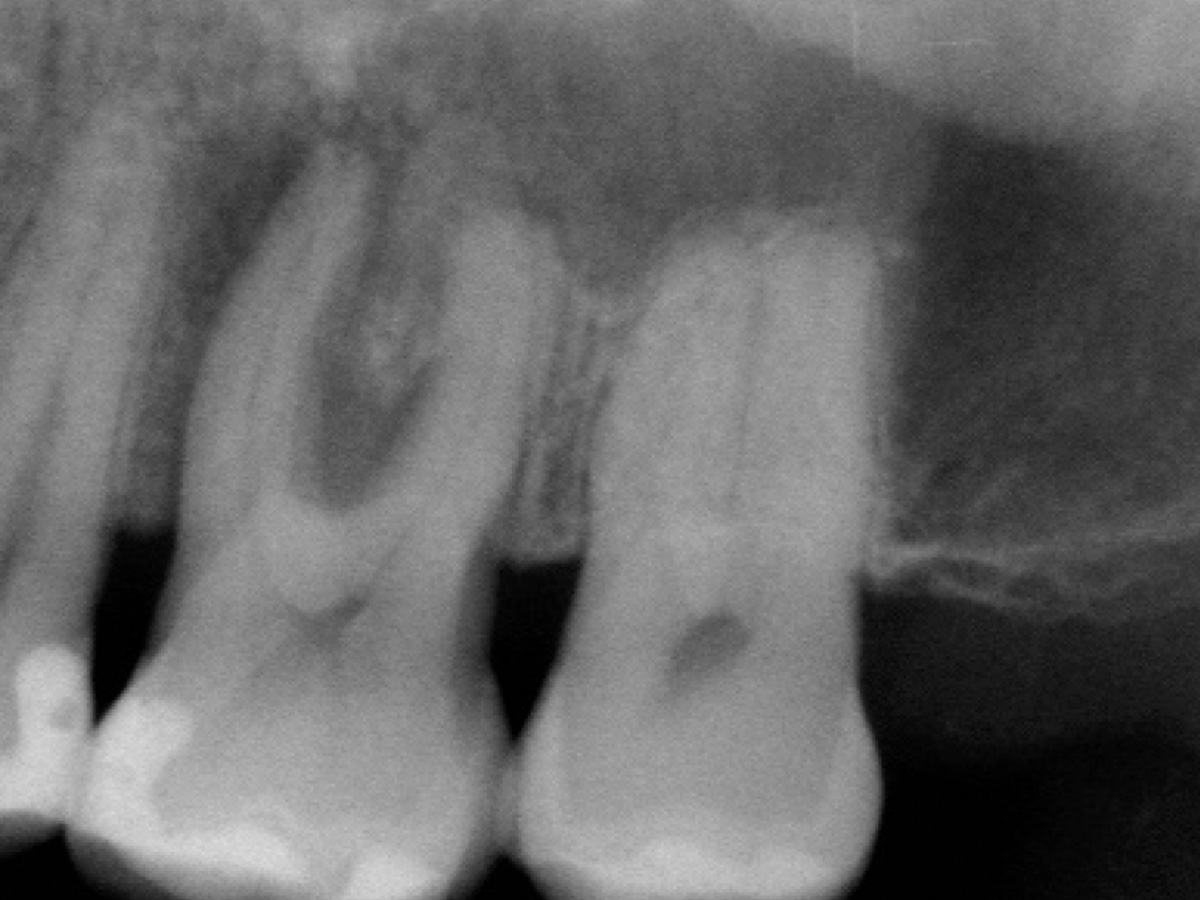

Abbildung 2

Röntgenologische Ausgangssituation Zahn 26: Komplexer parodontaler Knochenabbau im Furkationsbereich sowie periapikal der mesiobukkalen Wurzel.